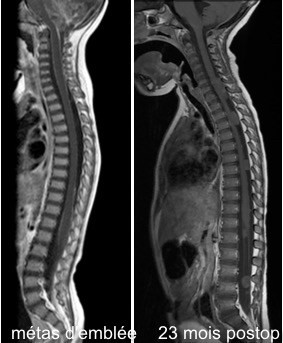

il existe rarement des métastases d’emblée, les métastases surviennent surtout lors des récidives, en particulier après irradiation focale qui prévient la récidive locale.

de même, une métastase unique n’est pas forcément une contre-indication à une réintervention, en particulier si elle fait courir un risque fonctionnel comme une métastase spinale.